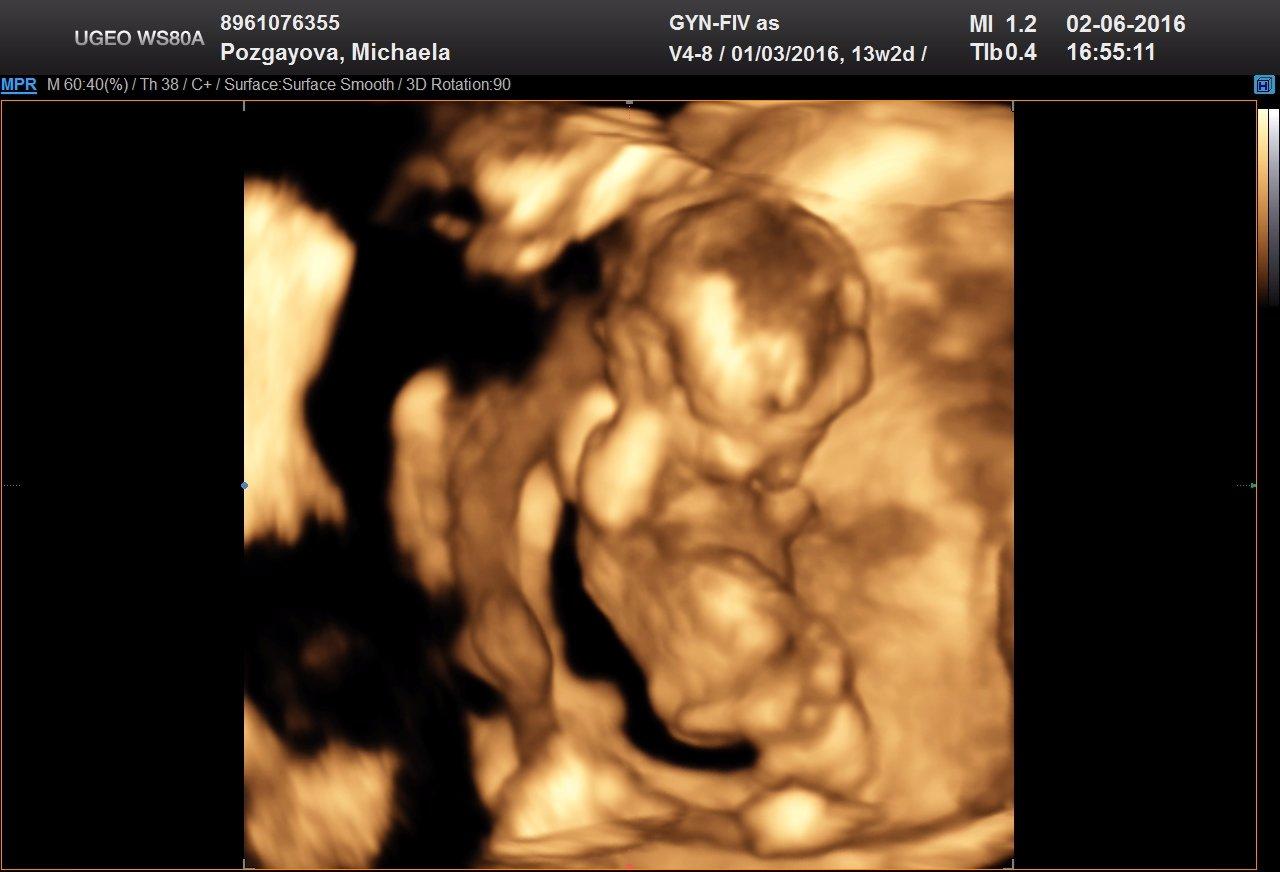

Tak tfuj tfuj tfuj drzim palce nech sa cimskor zadari. Skusim sa teda tu na dore spytat, ci to niekto nechce, darujem aj tak mi to len doma trci. Mam sa fajn prehupli sme sa do druheho trimestra, ale ani gram som nepribrala. Vo stvrtok sme boli s muzom na 3D utz tak sme sa narehotali sa tam to male tak hmyrilo, skakalo normalne rukami hromžilo 😀 uplne hyperaktivne, lekar povedal, ze si to mame uzit, kym je este v bruchu 😀 pozri aka super fotka, ze za hlavu sa drzi 😀

@miska_hryzka jeeej ako si hlavicku drzi ...asi sa uz teraz nerado foti....tak sa aj nadej opatruj a davaj na Vas pozor🙂 CMUK